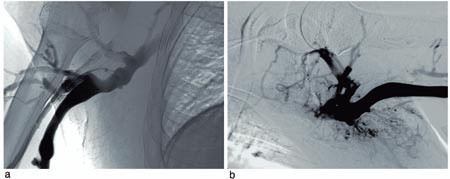

Røntgenundersøkelser. CT-undersøkelse viste trombemasser i v. jugularis og v. brachiocephalica på begge sider. Venografi bekreftet funnene og viste også trombemasser i v. subclavia på begge sider (fig 1). V. cava superior var også okkludert av trombemasser.

Behandling og forløp. Trombolysekateter (5F Jetlysis, Angiomed, BardInc, Karlsruhe, Tyskland) ble først lagt inn fra høyre arm, og det ble gitt alteplase 1 mg/t og samtidig heparininfusjon i trombolysekateteret. Bolusdose av alteplase ble ikke anvendt, da pasienten var antikoagulasjonsbehandlet med warfarin. Venografi etter ett døgn viste fin rekanalisering av høyresidige overarmsvener og delvis rekanalisering av de venstresidige overarmsvener samt v. cava superior. En subtotal stenose i v. cava superior ble avdekket (fig 2 a). Lumen i det stenoserte området hadde en diameter på 2 – 3 mm, og spissen av shunten endte i dette området (fig 2 a). Det ble satt inn en stent (14 x 40 mm Symphoni stent, Boston Scientific, USA) som ble dilatert til 10 mm (fig 2 b). Trombolysekateter ble så lagt inn fra venstre arm, og det ble gitt infusjon av alteplase og heparin. Venografikontroll viste komplett trombolyse etter totalt to døgns trombolytisk behandling. Pasienten ble behandlet med lavmolekylært heparin og warfarin inntil INR hadde vært i terapeutisk område (2,5 – 3,5) i to døgn. Ved utskrivning to uker etter innleggelse var pasienten fullstendig restituert. Ved kontroll etter seks måneder var han klinisk i fin form, og venografi viste åpne vener.

Behandlingseffekt ved lokal trombolytisk behandling evalueres med daglig venografi. Dette vil kunne avdekke anatomiske forhold som disponerer for trombosering og umiddelbart være tilgjengelig for intervensjon. Hos vår pasient ble det påvist stenose i v. cava superior, som ble dilatert og stentet. Intervensjonen med dilatasjon og stenting vil sannsynligvis være svært viktig for å unngå ny trombose i det aktuelle området.